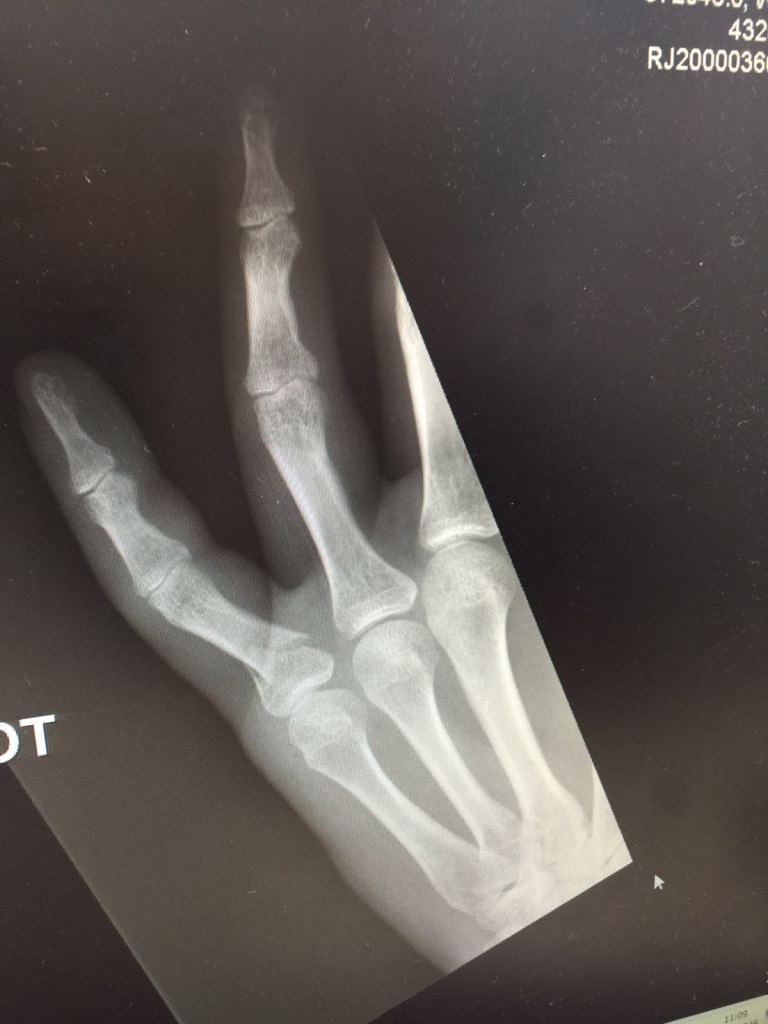

After suffering a tough month, the Ramblas headed to Chevening with the aim of starting July off with a bang. However, they were dealt a hammer blow when an already depleted squad was reduced to seven available players after skipper Johnny Stocks had to pull out with a broken thumb and his brother Laurie (looking to make his first Ramblas appearance in two years) couldn’t make the trip due to a broken car. Luckily, Chris Hollands of Locksbottom answered the distress call, and the Ramblas arrived at the ground with eight players – including Ash Harriss in for his first game of the season.

Harriss and Cooper opened the batting, knowing that with only eight players, wickets were at a premium. Sadly, the Ramblas were dealt a blow in the third over when Cooper was struck by a beamer, breaking a finger. Gamely choosing to carry on, he initially struggled to get the opening bowlers away and left Harriss to do the bulk of the work.